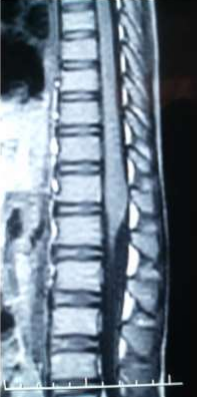

Image (1 & 2) Sagittal MRI of the spine of case (1) showing cauda eguia expansion and hyperintense patches of in the cauda equine of both T1 and T2 weighted MRI

Eight of the ten patients were diagnosed utilizing MRI which showed Dorsal 12 to Lumber 1 or 2 spinal cord swelling with hyper intense patches in T2 images , while the remaining two patient were diagnosed utilizing CT myelogram which showed Dorsal 12 to Lumber 1 or 2 spinal cord swelling.

Magnetic resonance imaging in spinal schistosomiasis usually shows swollen conus and epiconus beside areas of hyper-signal in T2 and heterogeneous contrast enhancement[12]. Multinodular intramedullary contrast enhancement of the distal cord allowed accurate preoperative MR imaging diagnosis of spinal schistosomiasis[12]. Cerebrospinal fluid (CSF) may show changes in spinal schistosomiasis. Characteristic features are mild to moderate pleocytosis, presence of eosinophils, slight to moderate protein increase, elevated gamma globulin concentration and a positive immune assay. These abnormalities are not always, accidentally schistosomal ovae may appear in the cerebrospinal fluid [13].